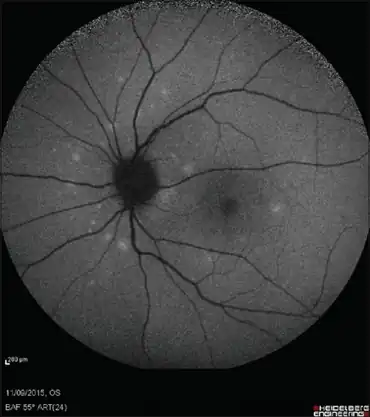

| Multiple white dots concentrated in the peripapillary area | |

Eye exam during the acute phase of the disease reveals multiple discrete white to orange spots at the level of the RPE or deep retina, typically in a perifoveal location (around the fovea). Optic disc oedema may also seen occasionally.[2]

- Fundus autofluorescence (FAF) has been shown to be a noninvasive method to demonstrate the subretinal spots in MEWDS.